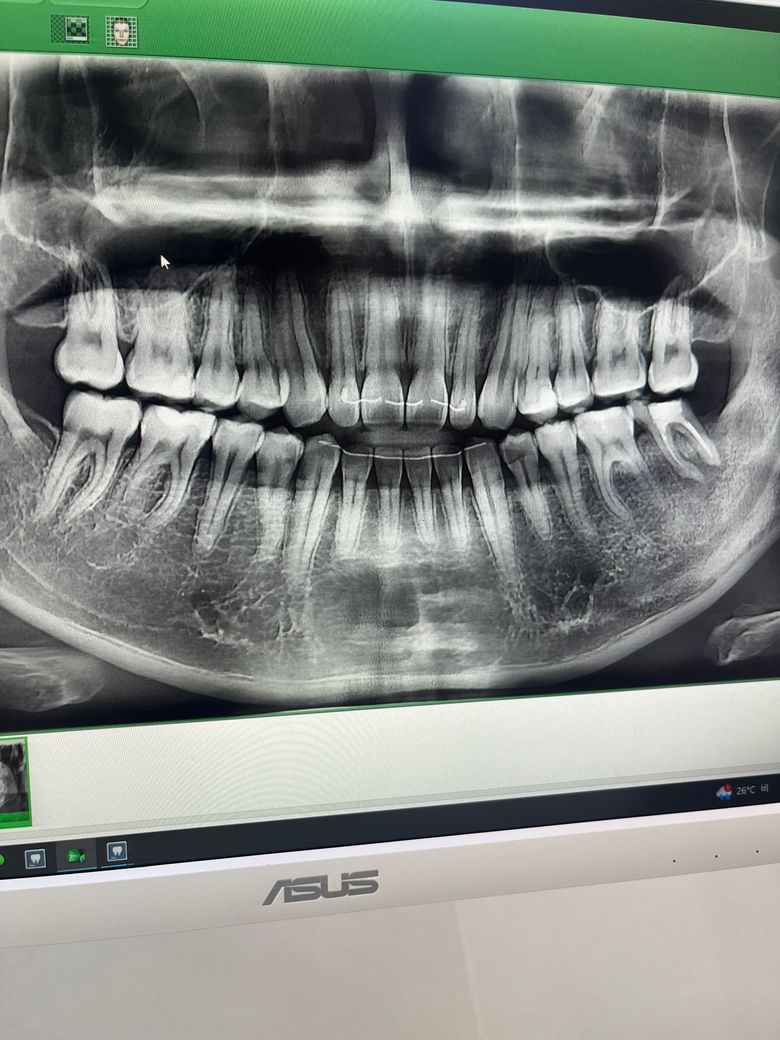

왼쪽 아래 맨끝 어금니를 10년전쯤 신경치료하고 크라운으로 씌우지 않고 계속 써왔는데 뿌리끝에 고름주머니가 생겨서 임플란트를 해야할 것 같다고 했는데 젊은 나이에 임플란트보다는 재신경치료가 가능하다면 그게 낫지 않을까해서 여쭤봅니다. 치아삭제가 많이 되긴 했지만 재신경치료가 가능할까요? 가능하더라도 임플란트가 더 좋을까요?

• 1번 째 사진